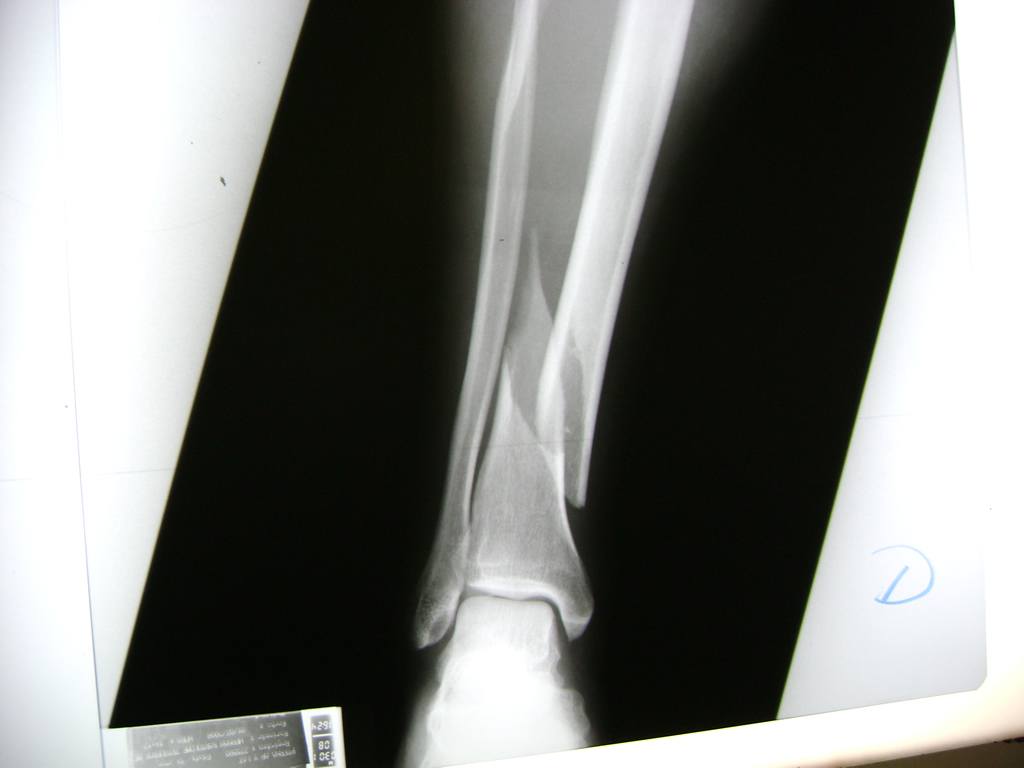

Cirugías de Peroné y Tibia

Aunque cada uno de estos huesos puede fracturarse por separado, normalmente la rotura es una lesión que se produce de forma conjunta

La mayor parte de las roturas implican a la parte proximal del hueso (parte del hueso próximo a la rodilla) o a la parte distal (parte del hueso cerca del tobillo).

Debido a la fina cobertura de piel que recubre la tibia y el peroné, las fracturas generalmente son abiertas, es decir, el hueso roto rasga la piel, atravesándola. Las fracturas de tibia y peroné generalmente se producen por un fuerte impacto o torsión.